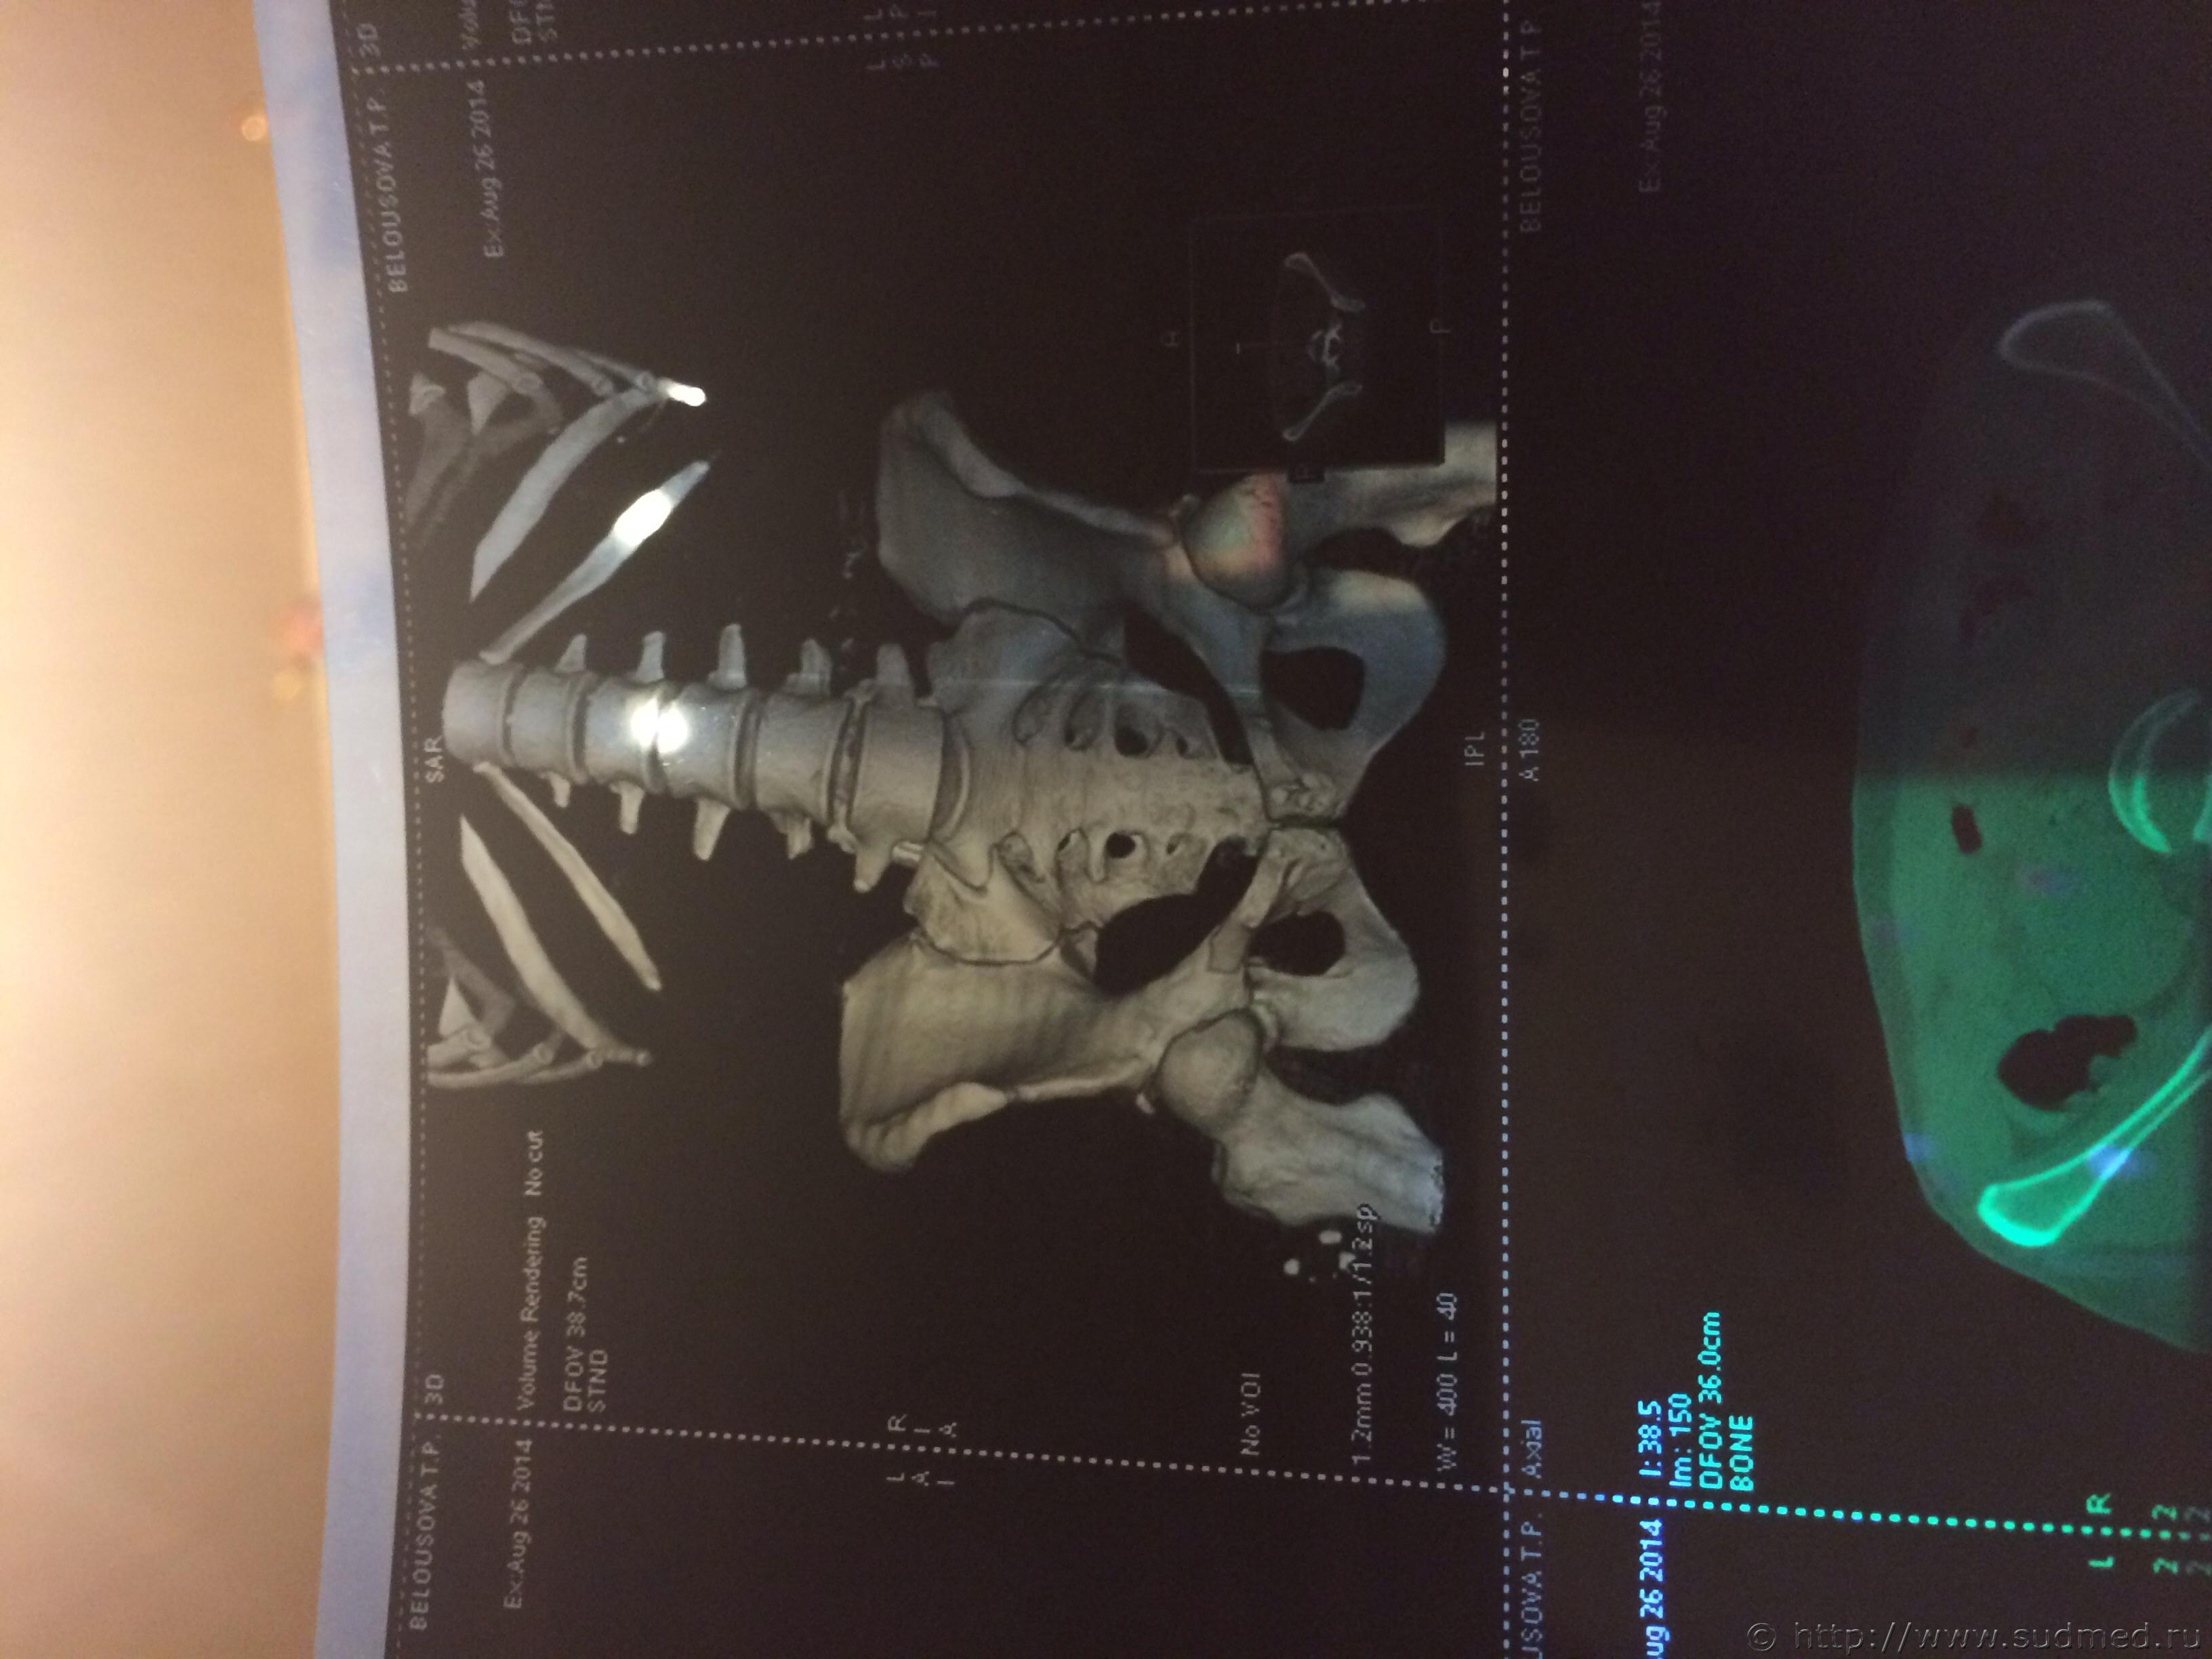

Спасибо! У меня результаты КТ, ошиблась)

КТ

Как мне видится - вертикальный перелом крестца. Тяжкий вред.

Впрочем, оставляю небольшую вероятность, что я не видел все сканы, да и качество их здесь, разумеется, хуже, чем изображение на пленке или на экране компьютера у врача, работающего на томографе.